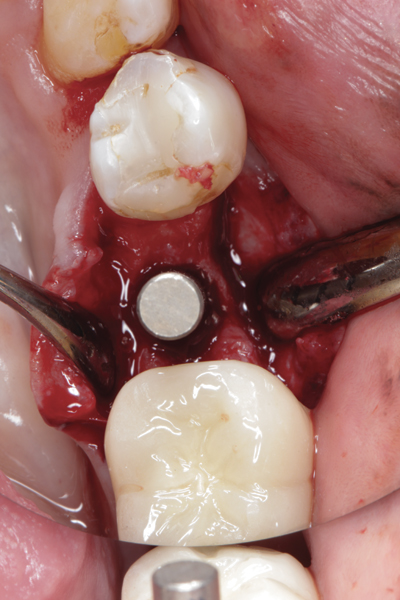

Fig 17. Bone graft was placed in the socket and a d-PTFE barrier was used to cover the graft. The bone graft material was placed beyond the alveolar housing to accommodate shrinkage of graft material and to facilitate attaining a wide alveolar ridge. The barrier was removed after 6 weeks.

Figure 17

Fig 19. Implant inserted into healed ridge.

Figure 19